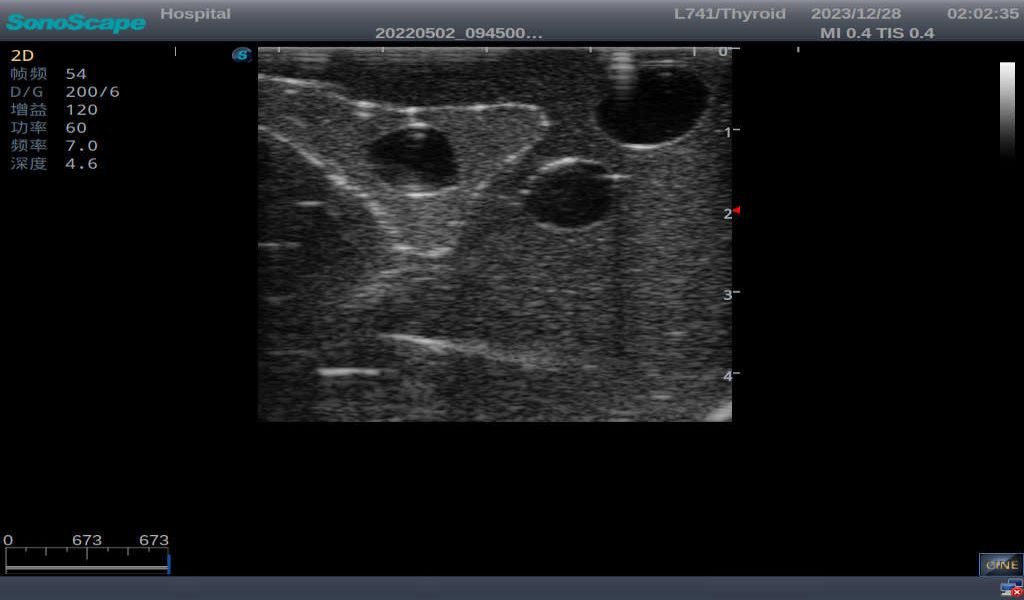

3)       It comes with four (4) thyroid modules and can show five (5) ultrasonic images: normal thyroid, thyroid adenoma, thyroid cancer, nodular goiter, thyroid cyst

Normal thyroid with homogeneous parenchymal echo and well-defined capsule

Thyroid adenoma with well-defined border and smooth uniform halo

Thyroid cyst, which fluid area, dark and echo-free area can be seen